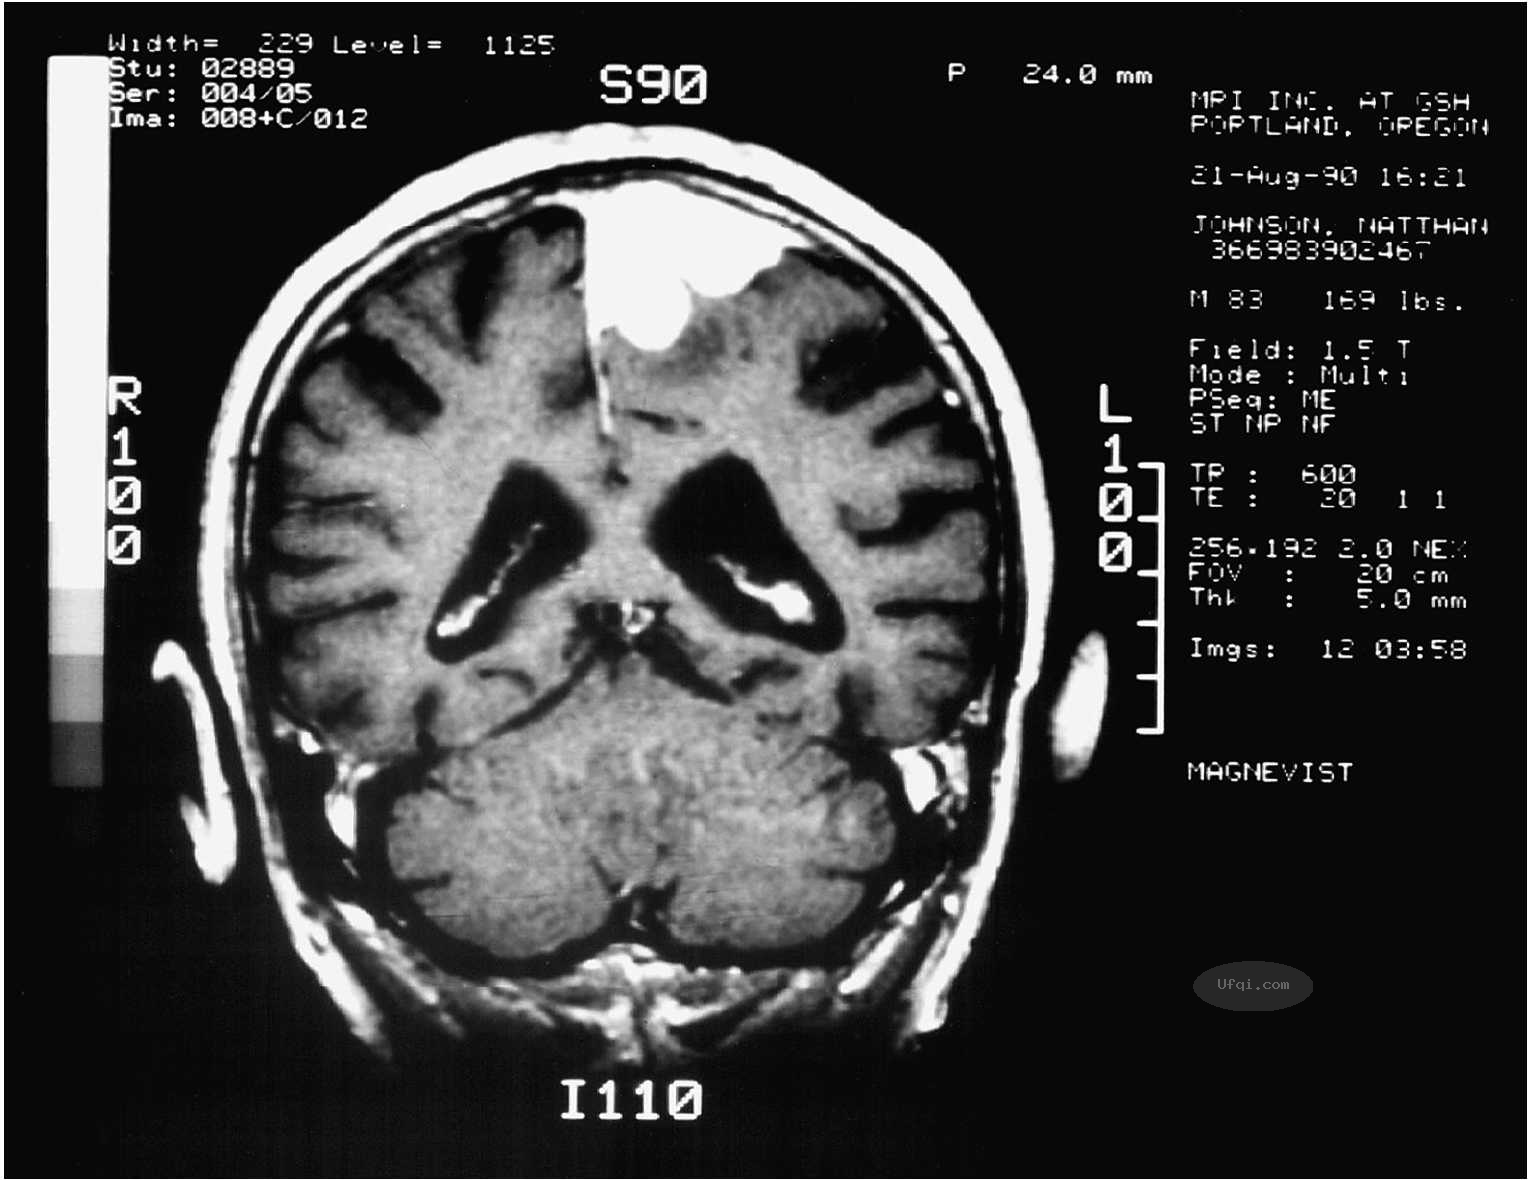

例如,亨利·莫莱森(HenryMolaison)的悲惨故事证明了这一点。亨利·莫莱森更广为人知的名字是H.M.(为了保护他的隐私,在他生前,别人都用首字母来称呼他)。

1953年,当时H.M.二十刚出头,为了治疗已经威胁到他生命的频繁发作的癫痫,他接受了一项激进的、实验性的脑手术(Hilts,1995)。这项手术切除了他的脑两侧的大部分海马,成功减少了癫痫发作的次数。

不幸的是,这项手术也产生了一个不可预测的、灾难性的副作用:手术之后,新的经历在事情发生之后就会立即从他的记忆中消失,但他对手术之前的事情的记忆完好无损。

在他的余生中,当他试图回忆1953年之后的事情时,得到的是一片空白。他甚至不能记住每天照顾他的人。

直到2008年去世之前,他还相信自己活在1953年。这个故事以及其他确凿证据表明,虽然海马不是记忆存储的地方,但是它对于创造新的记忆至关重要。

海马(左右半球各有一个)对于创建新的记忆至关重要,在空间记忆方面也起关键作用。